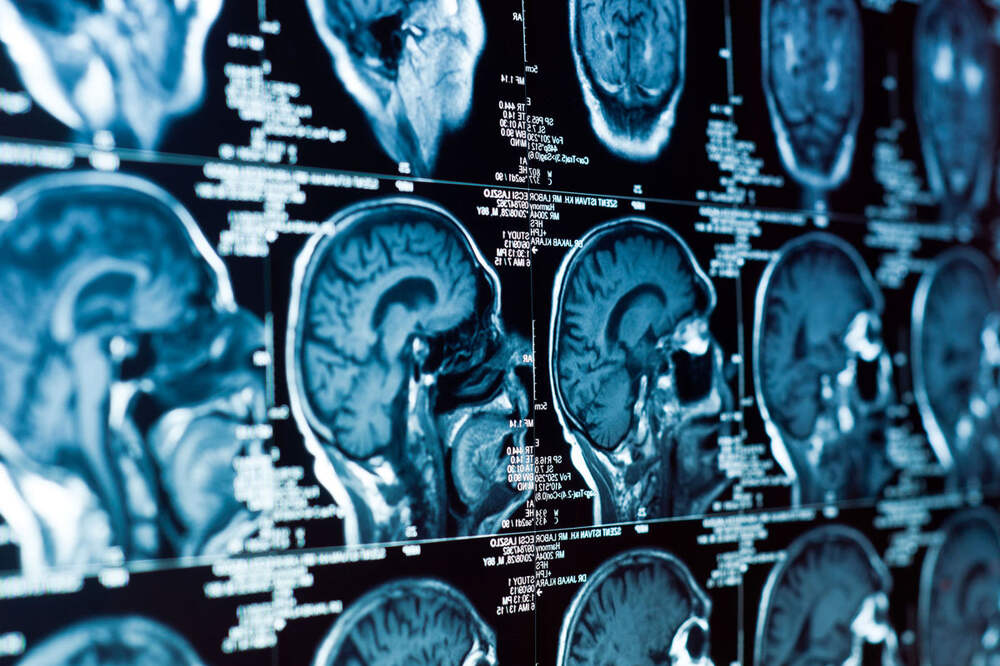

Нейробиологи объяснили забывание близких при болезни Альцгеймера и нашли способ этого не допустить

Открытия, которые могут помочь в разработке новых вариантов терапии для пациентов с болезнью Альцгеймера, ученые представили в статье, опубликованной в журнале Alzheimer’s & Dementia. Ранее эта группа исследователей из медицинского вуза при Виргинском университете (США) изучала так называемые